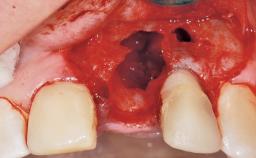

A 30-year-old female patient had lost tooth 21 and was referred to our clinic for consultation and treatment. Due to advanced apical infection, tooth 21 had been extracted two months earlier at another clinic and an acrylic-resin tooth had been bonded to the adjacent teeth. The patient desired implant treatment to avoid any damage to the adjacent natural teeth. While the patient had no history of any systemic disorder, she was a heavy smoker and exhibited medium to advanced periodontitis in the entire jaw. After the initial treatment to achieve a pocket probing depth of less than 4 mm and no bleeding on probing, a decrease in the height of the papillae mesial and distal to the extraction site and overall gingival recession were observed.